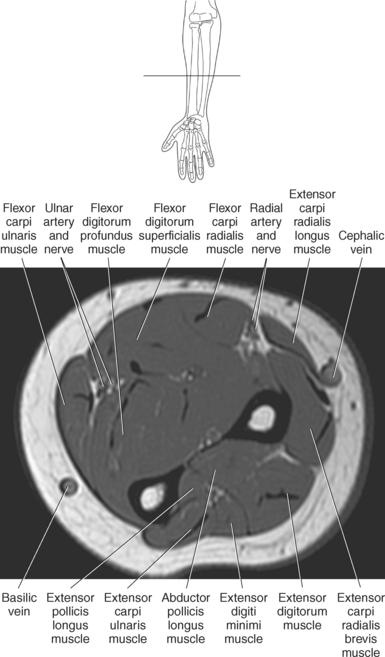

The brachial plexus, also described in Chapter 4, is a large network of nerves that innervate the upper limb (Figures 9.38 and 9.148). It extends from the neck into the axilla. The brachial plexus is formed by the union of the ventral rami of nerves C5-C8 and the greater part of the T1 ventral ramus. The ventral rami from C5 and C6 unite to form a superior trunk, the ventral ramus of C7 continues as the middle trunk, and the ventral rami of C8 and T1 unite to form an inferior trunk. Each of these trunks divides into an anterior and posterior division. The anterior divisions supply the anterior (flexor) parts of the upper limb, and the posterior divisions supply the posterior (extensor) parts of the upper limb. These divisions form three cords (posterior, lateral, and medial) that continue to divide to form the median, ulnar, musculocutaneous, and radial nerves (sequential Figures 9.59 through 9.67 and 9.87 through 9.95). These nerves supply the muscles of the forearm and hand. The median nerve descends the cubital fossa deep to the median cubital vein. It supplies the pronator teres muscle of the arm and all the superficial and deep flexor muscles of the forearm, except the flexor carpi ulnaris muscle. It gives off an anterior interosseous branch that descends within the forearm to supply the flexor digitorum profundus muscle. The median nerve courses through the carpal tunnel of the wrist, typically superficial to the flexor tendons (Figure 9.147). It supplies flexors of the hand, skin of the wrist, thenar eminence, palm of the hand, and sides of the first three digits and lateral half of the fourth. At the elbow, the ulnar nerve passes between the medial epicondyle of the humerus and the olecranon process within the cubital tunnel to enter the medial side of the flexor compartment of the forearm (Figure 9.148). Posterior to the medial epicondyle, the ulnar nerve is superficial and easily palpable. It supplies the flexor carpi ulnaris muscle and the medial side of the flexor digitorum profundus muscle in the forearm before entering the hand. The ulnar nerve passes under the flexor retinaculum, along with the ulnar artery, to enter the palmar compartment of the hand (Figure 9.147). At this point, the ulnar nerve divides into superficial and deep terminal branches that supply the ulnar flexors of the hand as well as the skin on the medial side of the palm, medial half of the dorsum of the hand, fifth digit, and medial half of the fourth digit. The musculocutaneous nerve descends to the lateral side of the arm and elbow to innervate the flexors in the arm and the skin of the forearm, wrist, and thenar region of the hand (Figure 9.146). It emits branches that supply both heads of the biceps brachii muscle, the brachialis muscle, and the elbow joint. It innervates the skin of the dorsal surface of the arm. A continuation of the musculocutaneous nerve is the lateral cutaneous nerve, which terminates into cutaneous branches that supply the skin covering the radial side of the wrist and the thenar eminence. The radial nerve is the largest branch of the brachial plexus. It passes inferolaterally around the body of the humerus in the radial groove (Figure 9.146). It continues inferiorly between the brachialis and brachioradialis muscles to the level of the lateral epicondyle of the humerus, where it divides into deep and superficial branches. The deep branches supply all the extensors in the arm and forearm, and the cutaneous branches innervate the skin on the dorsal side of the arm and hand. The superficial branch, the direct continuation of the radial nerve, is entirely sensory. It supplies skin and fascia over the lateral two thirds of the dorsum of the hand, the dorsum of the thumb, and proximal parts of the lateral three and one half digits on their dorsal surfaces (Figures 9.57 through 9.67, 9.87 through 9.98, and 9.146 and 9.147).